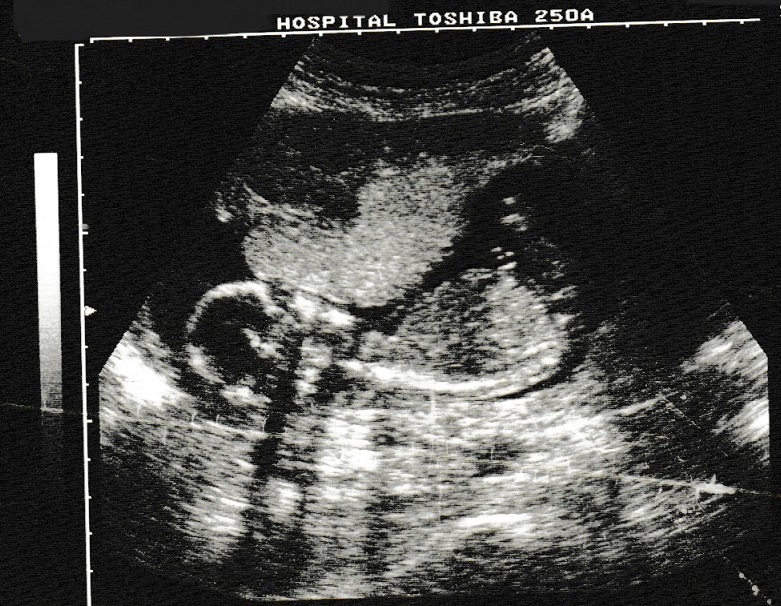

Here are the photos taken this morning, I do hope you can make sense of them on the fax.

The nice lady at the hospital who took my photo said that I am the right size for Mummy’s dates so I should be here to see you on the 2nd of June. Mummy and Daddy could see me very clearly on the screen even though I was moving around a lot. They could see my face and spine and my little heart going like the clappers. Both Mummy and Daddy are sure I am a boy but I kept my little legs tightly crossed so they couldn’t really see anyway.

My brain looks very big compared to my body, Daddy said it’s already bigger than his brain, Mummy thought that was funny.